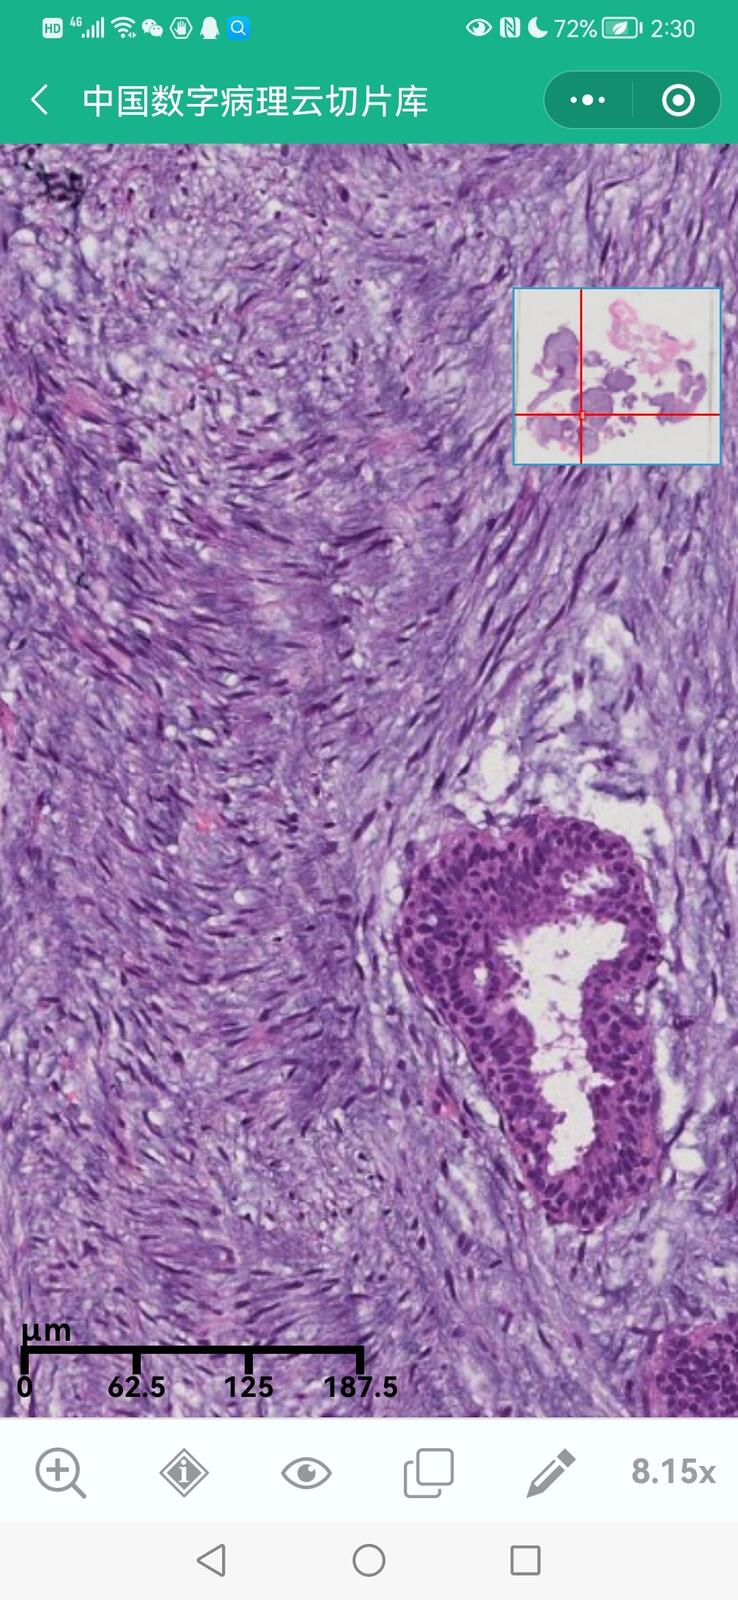

乳腺黏液性囊腺瘤伴导管内癌

乳腺多形性脂肪肉瘤

乳腺叶状囊肉瘤

乳腺分泌性癌(29岁)